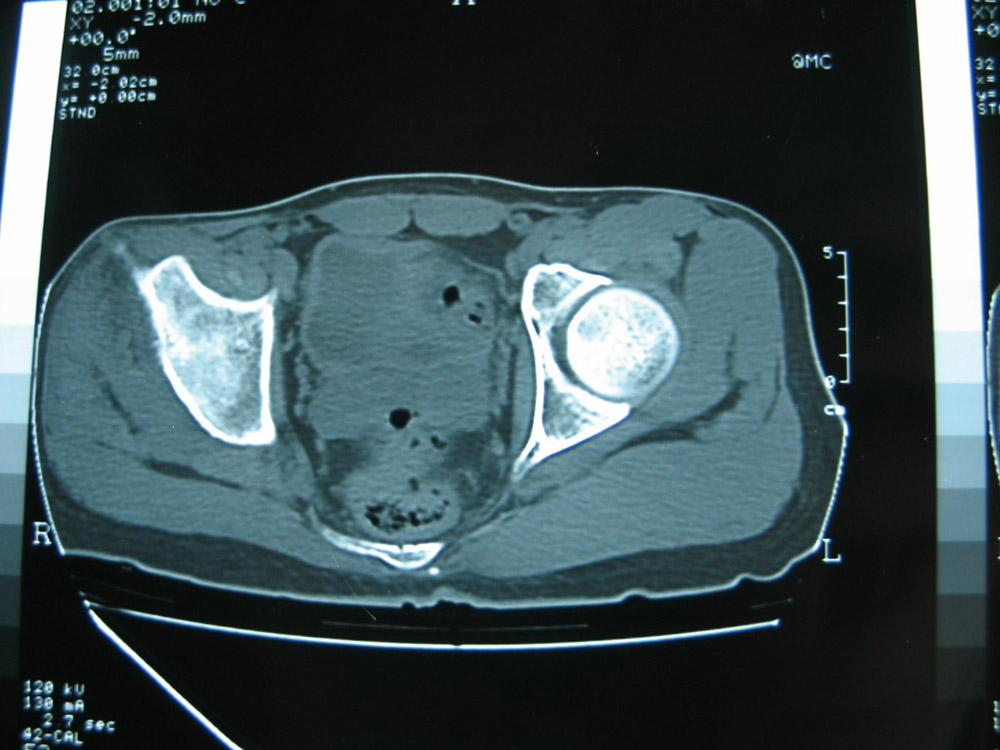

以下是引用卜一在2007-1-25 16:33:00的发言:[br]右侧髋关节股骨头及髋臼骨骨小梁疏松 粗糟,股骨头外形毛糟,软组织似肿胀,间隙略变窄.考虑:1 髋关节结核可能性大.2 缺血性坏死?3 化脓性髋关节炎?

以下是引用hhcckk在2007-1-25 17:18:00的发言:[br][br]支持髋关节结核,[br]依据关节面破坏,有脓肿,脓腔内有钙化,关节周围增生不明显,鉴别[br]1化脓性的病变增生明显,临床上有高热[br]2创伤引起的关节炎,无菌坏死不会引起关节面的破坏,而且不会在这么短的时间内出现[br]